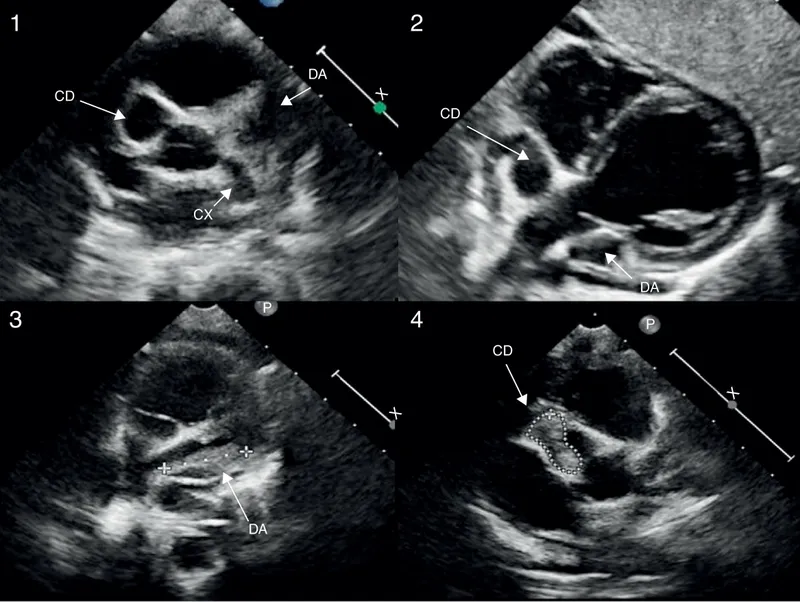

- Diagnosis & monitoring via Echocardiography at baseline, 1-2 weeks, and 4-6 weeks after treatment.

- Classified by z-scores (internal diameter):

- Small: z ≥2.5 to <5

- Medium: z ≥5 to <10

- Giant: z ≥10 or >8 mm diameter.

⭐ Giant aneurysms have the highest risk of thrombosis/stenosis (~50%) and mandate long-term anticoagulation.

- Echocardiography is the gold standard for diagnosis and serial monitoring of coronary arteries.